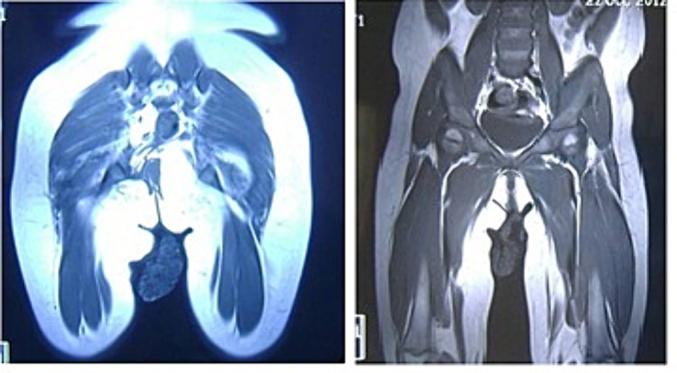

Lipoblastoma is a benign neoplasm of immature fat tissue occurring in infants. The gluteal region location is relatively rare. Imaging, especially MRI, is helpful in diagnosis and preoperative evaluation. An adequate pathological examination could bring huge benefits. Total surgical resection is the treatment of choice. Subtotal resection and "wait and see policy" may be discussed for highly risky intervention.

脂肪母细胞瘤是一种发生于婴儿的未成熟脂肪组织的良性肿瘤。位于臀区相对少见。影像学检查,尤其是磁共振成像(MRI),有助于诊断和术前评估。充分的病理检查可能带来巨大益处。手术全切是首选治疗方法。对于高风险干预,可讨论次全切除和“观察等待”策略。